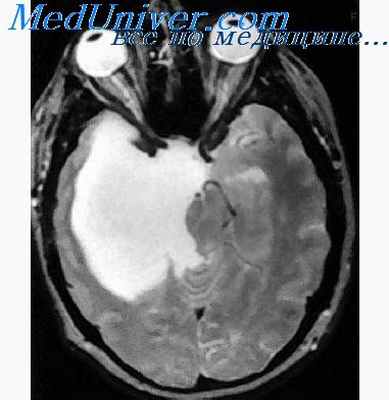

- С помощью диагностической визуализации — компьютерной томографии (КТ) и магнитно-резонансной томографии (МРТ) — получают детализированные изображения головного и спинного мозга. Врачи могут увидеть размеры и расположение опухоли и лучше понять, какие участки мозга оказались затронуты. МРТ часто предпочтительнее, поскольку обычно обеспечивает более четкую визуализацию опухолей головного мозга.

Краниофарингиома на МРТ в осевой проекции

- КТ и МРТ. Диагностические методы визуализации, которые позволяют получить точное изображение головного мозга. Это помогает определить размер и локализацию опухоли, какие ткани она затронула. МРТ при определении краниофарингиомы гипофиза дает более четкую картинку;